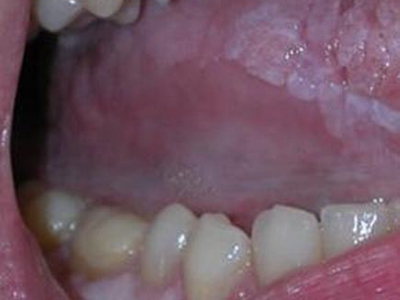

舌扁平苔藓一般认为发生率仅次于颊部扁平苔藓,好发于中年人,女性高于男性,且发病率随着年龄的增加而增加。病变多发生在舌前2/3区域,包括舌尖、舌缘和舌腹部。损害多样,一般较局限。

舌扁平苔藓的损害多样,舌背早期损害多为丘疹斑点状,灰白透蓝,开始时侵及丝状乳头顶部,而乳头下半部黏膜正常,以后整个乳头受累。由白色丘疹组成环网状损害,从中央逐渐向周围及深层扩展,并形成圆形或椭圆形灰白斑块损害,触之稍粗糙。舌乳头由萎缩逐渐光秃,向周围扩展,形成中央上皮萎缩变薄,呈鲜红或暗红平滑斑。在此基础上可发生糜烂,糜烂面愈合后,舌乳头恢复则非常缓慢。

舌背病损也可呈现乳头增殖角化和部分萎缩混合病损。病损可为孤立存在,也可呈不规则形状散在分布。舌腹部病损多呈网状、树枝状或线条纹,单侧或左右对称发生。

发生于舌尖及口底部的扁平苔藓较少见,可侵犯舌系带,并向前发展。舌侧缘、舌腹部扁平苔藓病损如为长期充血红斑,有斑点状增生突起、糜烂溃疡者,应注意观察或及时进行活体组织检查。